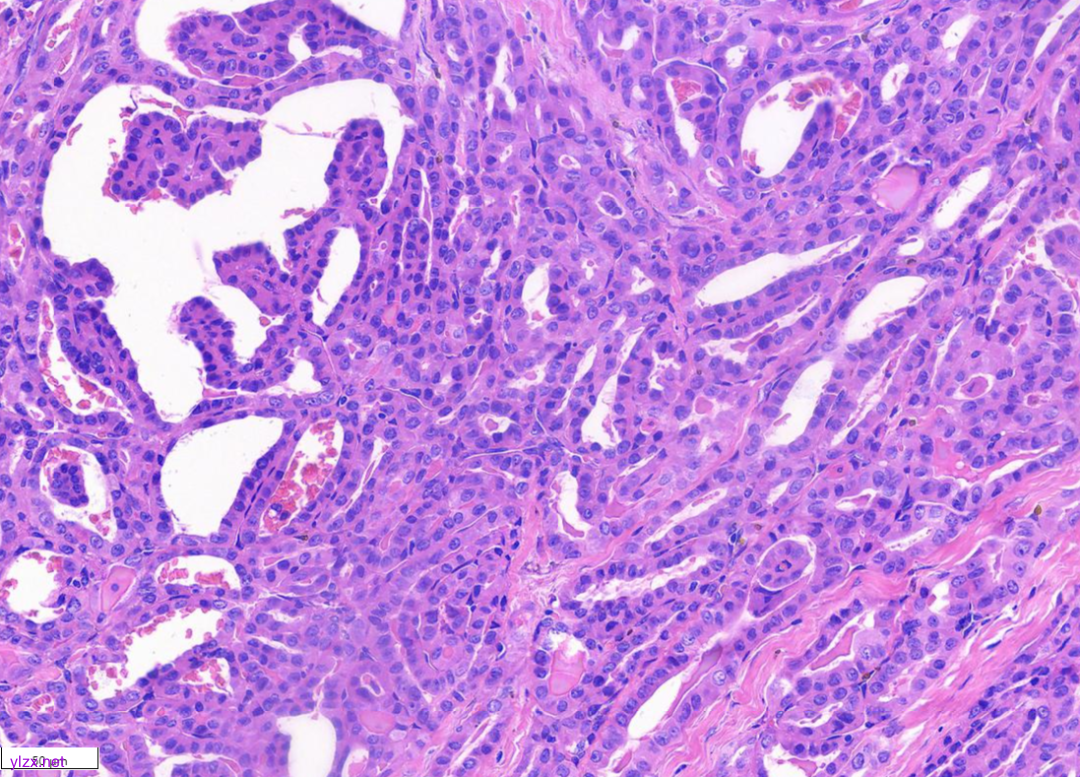

低倍镜下甲状腺乳头状癌区域与间变性癌鳞状细胞样亚型区域分界清,(图1)。低倍镜下,可见甲状腺乳头状癌呈乳头状、片状、索状分布,间质硬化(图2)。20倍镜,肿瘤细胞排列呈“铁轨”样,细胞立方形,细胞质丰富,淡嗜酸,细胞核圆,大小一致,染色质粗,核位于基底,可见小核仁,核内假包含体(图3)。鳞癌样区域(HEx10)肿瘤细胞呈多边形,梭形、上皮样,胞浆嗜酸,可见不全角化,肿瘤细胞间见脂褐素,肿瘤细胞侵袭性强,浸润至周围脂肪组织(图4、图5)。

图3 显示高细胞亚型区域(HEx10)